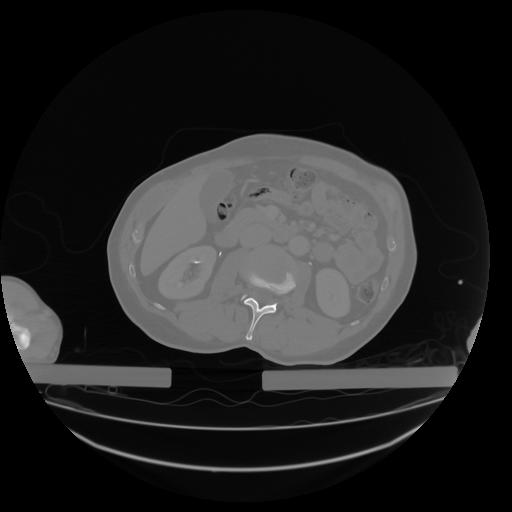

27 CUERPO,CE,Axial,3.0,CUERPO,,